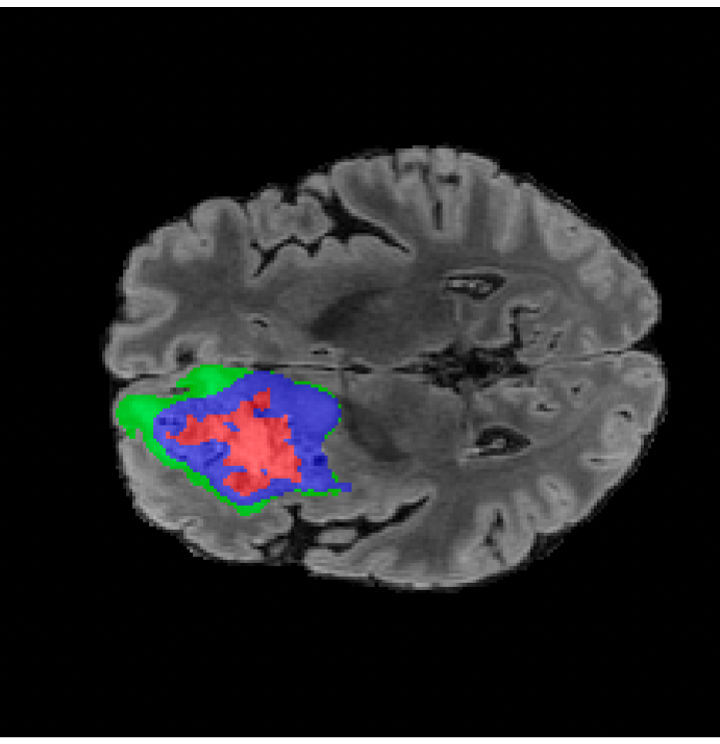

Tumour Information Preservation. For the brain tumor segmentation, we use a Swin UNETR model[27, 70], trained with random rotation, and intensity as data augmentation. In Figure 5, we highlight the tumor profiles of the generated MRIs compared to the ground truth tumour profile. In the test set with human ground-truth annotations (), the real MRI Dice score is 85.15 while the generated MRIs from a single slice have a dice score of 83.09. This shows how the generated MRIs indeed preserve the tumor information and can act as an affordable and informative pseudo-MRI, before conducting an actual costly MRI examination in hospitals.

B.4 Tumour Information Preservation

On the test set with human ground-truth annotations (), the brain volumes generated from single slice input preserve the volume of the different tumour components (paired t-test, for all 3 classes) (see Table 3). The real MRI Dice scores are put for reference to our generated MRIs. X-Diffusion outperforms baselines TPDM [36] and ScoreMRI [18] in tumour preservation (see Table 3 and Figure 12). We ran experiments comparing the tumour segmentation Dice Score varying X-Diffusion configurations. The multi-slice input X-Diffusion achieves a marginally better Dice Score than the single-slice input model (83.47 83.09). We also ran experiments with slice input used for volume reconstruction intersecting or not with tumour. We observe on average a drop of 6% Dice Score (see Table 3). Further away from the tumour the input slice for volume reconstruction is selected, and we observe a linear decrease in tumour segmentation Dice Score with the lowest value of 77.21 Dice Score (see Figure 15).